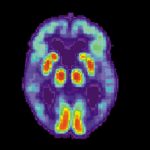

Az Uyku Alzheimer’ı Tetikliyor Olabilir!

Son yıllarda bilim insanları Alzheimer ve uyku arasındaki bağlantıyı anlamak adına önemli mesafeler kat etti. Şimdi ise Oregon Sağlık ve Bilim Üniversitesi'nden bir grup araştırmacı...